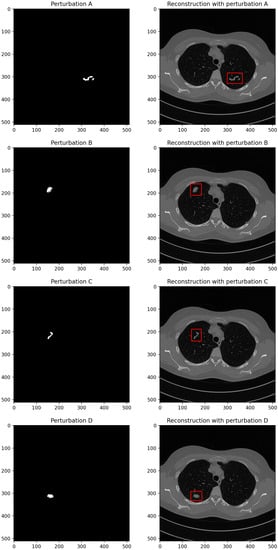

2.3. Reconstruction Perturbations